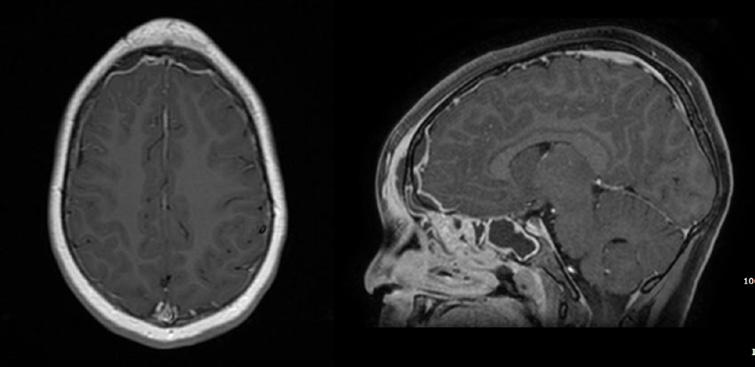

67 Cefalea… occhi aperti

Giuseppe Paviglianiti, Elisa Costantini, Gianluca Coscia, Floriana Di Marco, Vittorio Messina, Domenico Cipolla, Angelo Spataro